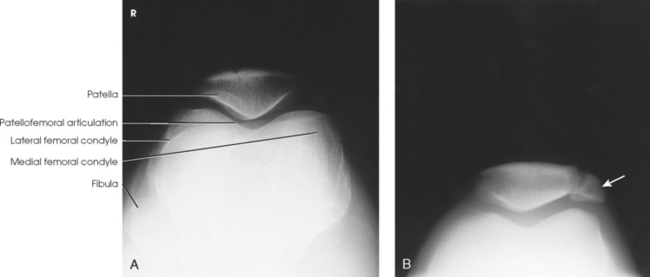

Structures shown: The resulting image shows a lateral projection of the patella and patellofemoral joint space (Figs. 6-150 and 6-151).

Structures shown: The tangential image shows subluxation of the patella and patellar fractures and allows radiologic assessment of the femoral condyles. Hughston recommended that both knees be examined for comparison (Fig. 6-153).

Structures shown: The bilateral tangential image shows an axial projection of the patellae and patellofemoral joints (Fig. 6-156). Because of the right-angle alignment of the IR and central ray, the patellae are seen as nondistorted, albeit slightly magnified, images.

Fig. 6-156 A, Normal tangential radiograph of congruent patellofemoral joints, showing patellae to be well centered with normal trabecular pattern. B, Abnormal tangential radiograph showing abnormally shallow intercondylar sulci, misshapen and laterally subluxated patellae, and incongruent patellofemoral joints (left worse than right). (Courtesy Alan J. Merchant.)